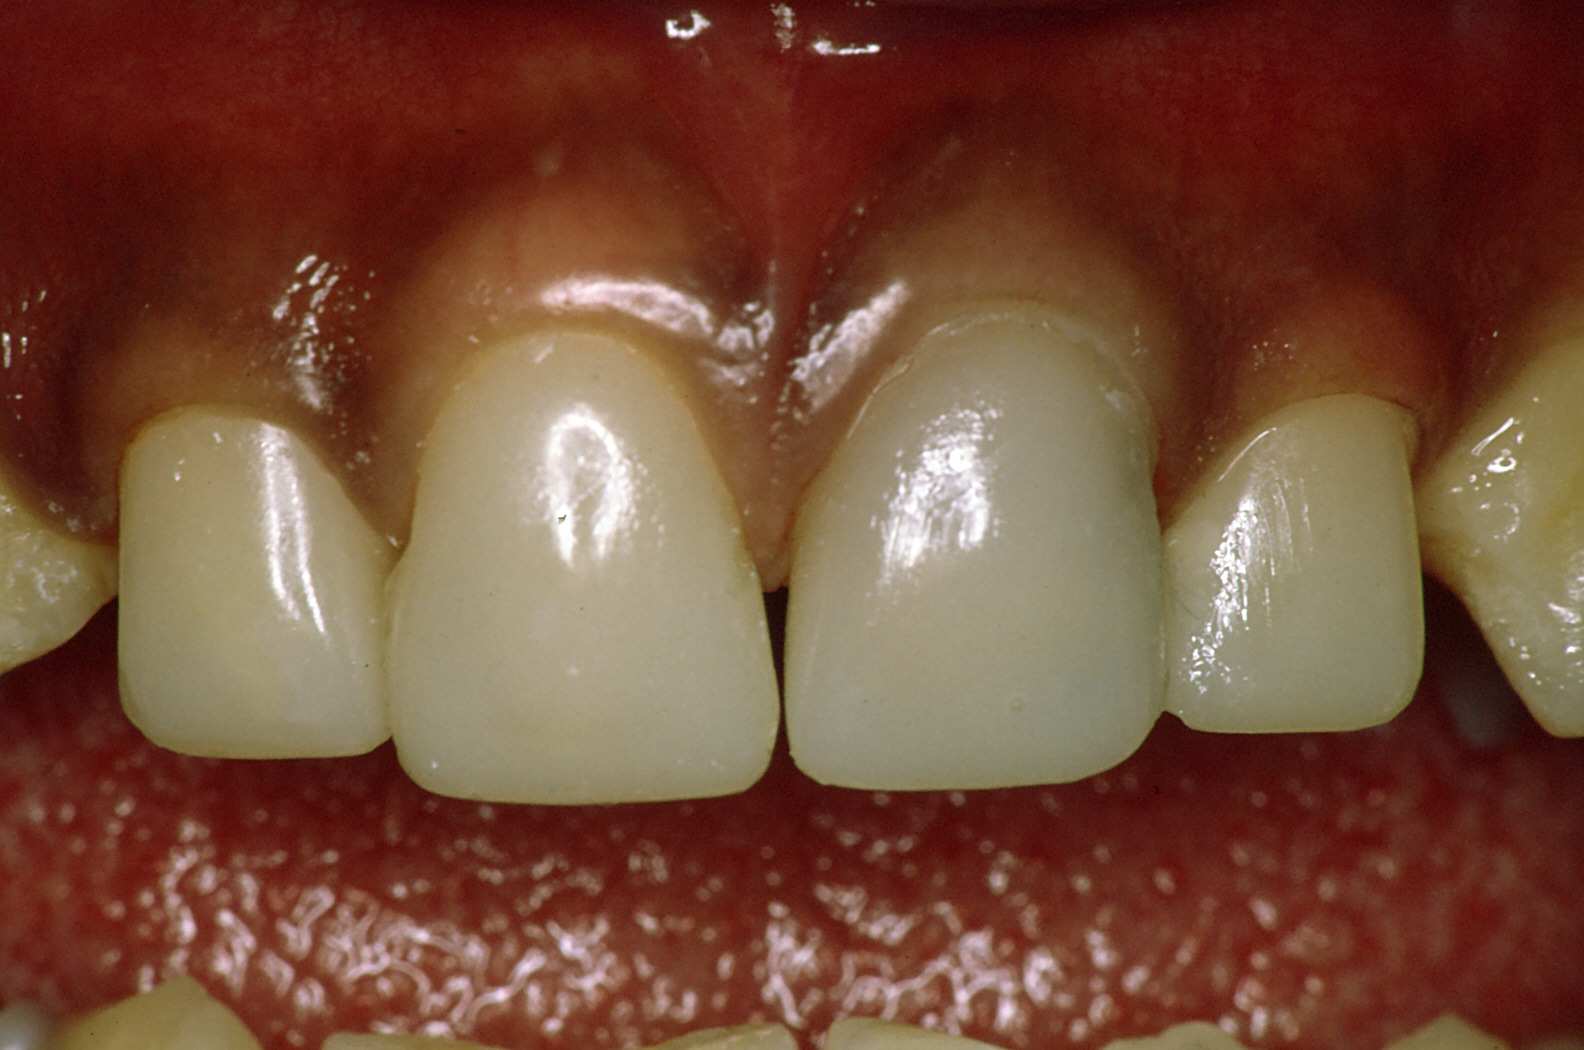

前歯の治療

「前歯は保険が効かない?」

こんな言葉昔は良く耳にしたのではないでしょうか。写真は同じ方です。保険で、それも歯はほとんど削っていません。

残念ながら欠点としては、変色すると言うことと、強度的に十分とはいえません。

金銭的な問題がクリアできる方は保険のきかないかぶせ物をお勧めします。変色の心配もなく、色合いはより歯に近くなり、強度も保険のものより高くなります。

「歯をかぶせる治療について」

保険、保険外(自費)、いくつかの選択肢があります。歯の状態、咬み合せ等により内容が変わります。この場では十分な説明ができませんので是非一度拝見させてください。

「保険が効かないものについて」

メタルボンドクラウンと言って、金属の枠を作り、それに焼き物をつけていく、もっともオーソドックスなものがあります。最近広まってきている「オールセラミックス」等は、メタルフリー(金属を使用しない)のもので、金属アレルギーのある方には特に朗報と言えると思います。メタルボンドクラウンや金属でかぶせる(金歯、銀歯)のに比べると歯を削る量が増えます。従って、症例によってはお勧めできないことがあります。それぞれに利点欠点が必ずあります。